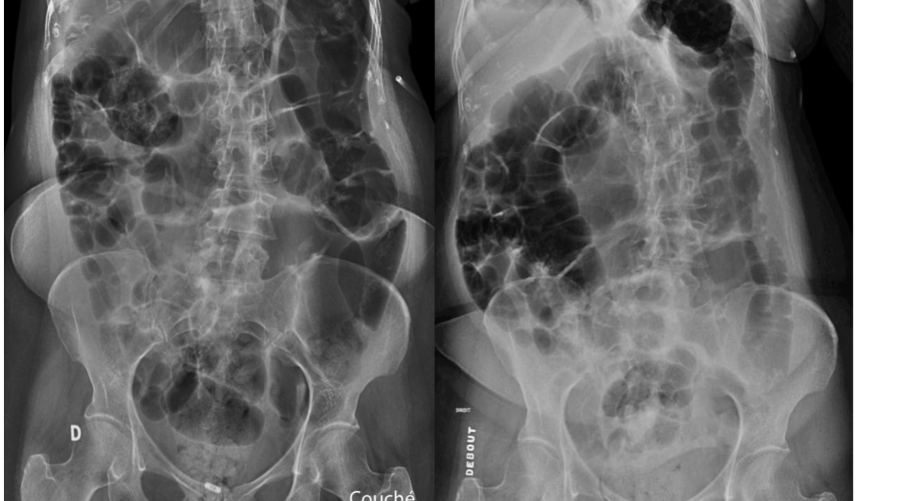

patho?

A

Illéus paralytique